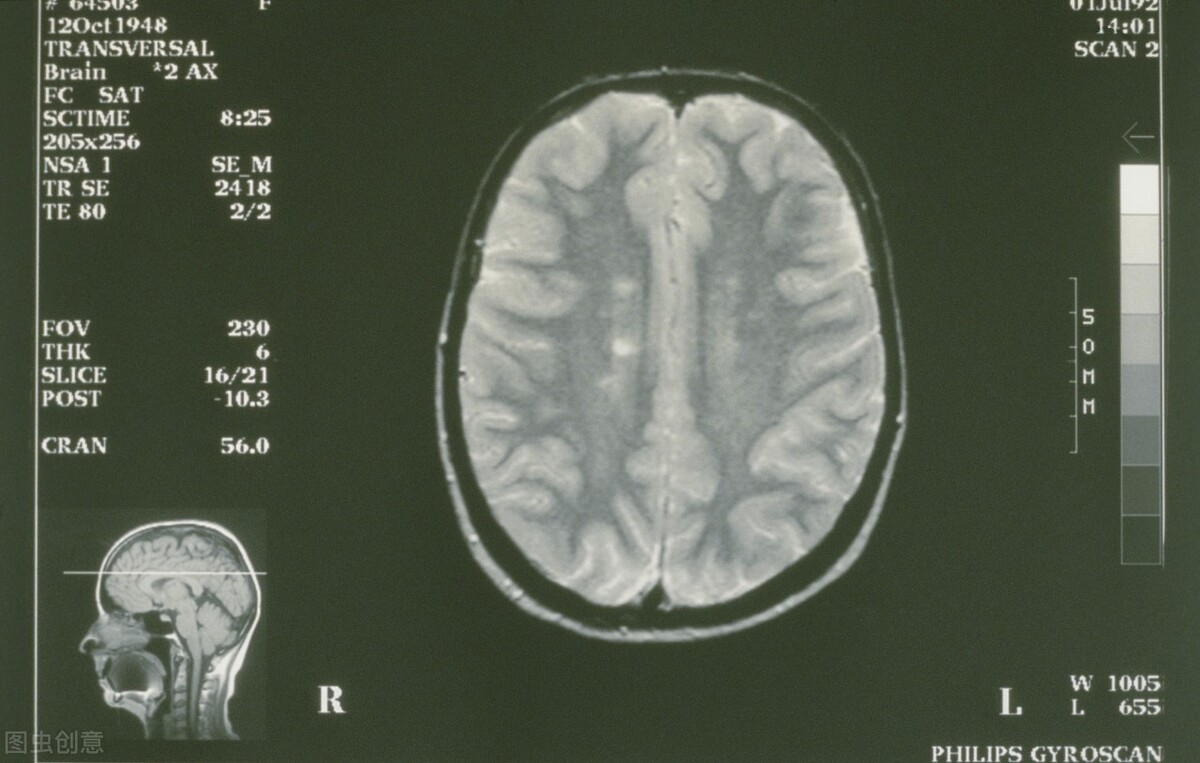

三、生理性脑萎缩。

很多人一看脑萎缩出现了,就害怕了,难道就是奔着老年痴呆去吗?

先别着急,脑萎缩并不一定都是严重的问题,很有可能是生理性的,换句话说就是正常现象。

大脑的衰老方式其实有很多,其中重要的一点,就是可以明显发现大脑萎缩。

在脑CT,或者颅脑核磁共振中可以看到,脑组织一点一点变小,这种萎缩通常都是比较正常的现象。

而且即使出现脑萎缩,很多人并没有什么感觉,也没有什么症状,仅仅是在体检中发现而已,对于这种情况并不需要太过担心,这是非常正常的现象。

可是,如果是阿尔兹海默症患者就该值得关注了,具体的治疗还是应该重视医生的建议。